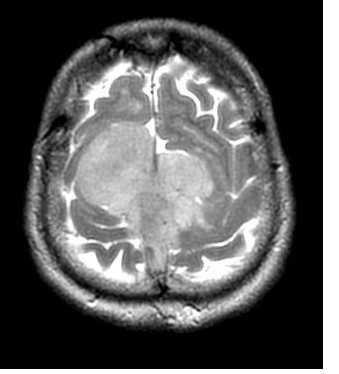

(б) МРТ, постконтрастное Т1-ВИ, корональный срез: определяются протяженное контрастирование «серпантинного» характера утолщенной мягкой мозговой оболочки (пиальный ангиоматоз) и увеличение субарахноидального пространства над правым большим полушарием головного мозга. Очевидна выраженная правосторонняя гемиатрофия головного мозга. (а) МРТ, постконтрастное Т1-ВИ, аксиальный срез: определяется классический синдром Стерджа-Вебера (ССВ) в виде атрофии правого большого полушария, увеличения размеров ипсилатерального сосудистого сплетения и распространенного пиального ангиоматоза, покрывающего практически всю поверхность полушария.

(б) МРТ, постконтрастное Т1-ВИ, более краниальный аксиальный срез: у того же пациента определяются схожие изменения. На данном изображении в субарахноидальном пространстве визуализируется скопление расширенных сосудов.